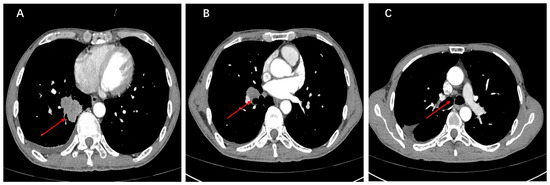

Mutation profiling of ctDNA from peripheral plasma collected one week after surgery and DNA obtained from formalin-fixed paraffin-embedded (FFPE) tumor tissue sections was performed using next-generation sequencing (NGS). The NGS tests, which utilized the LungTrak panel, targeted 139 lung cancer-related genes and were conducted at a centralized, CLIA-certified, and CAP-accredited clinical testing center (Nanjing Geneseeq Technology Inc., Nanjing, China). The sequencing platform used for the study was Illumina. A rare KIF13A-RET fusion involving exon 19 of KIF13A and exon 12 of RET was detected in tumor tissue (Figure 2). Mutations in the TP53, APC and MYC genes were also detected in the tissue sample. CtDNA was not identified in the peripheral plasma one week after surgery. Considering the patient’s long history of smoking and tumor staging, postoperative therapy was recommended. However, the patient declined adjuvant chemotherapy. After further discussion and collaborative decision-making, the patient was started on oral pralsetinib at a dose of 400 mg/d on postoperative day 84. One month after starting the medication, the patient experienced adverse reactions such as fatigue and loss of appetite, prompting a dose adjustment of pralsetinib to 300 mg/d. Upon the patient’s request, ctDNA was monitored at periodic intervals using LungTrak ctDNA testing. The patient’s ctDNA levels, measured using the assay above-mentioned, 7 and 206 days after surgery, were both 0.0% mutation allele frequency (MAF), with repeat ctDNA analysis 12 months after taking pralsetinib indicating persistently negative ctDNA at 0.0% MAF. Due to personal compliance issues, the patient became irregular in taking medication after one year of adherence. In Feburary 2023, after 20 months on pralsetinib therapy, ctDNA assessment identified detectable KIF13A-RET fusion 0.1% MAF. The finding in ctDNA level prompted a chest and upper abdominal enhanced CT scan, which did not reveal any signs of recurrence or metastasis. After 1 month of regular pralsetinib intake, ctDNA test no longer detected the RET fusion. However, repeat CT imaging 3 months later revealed a single nodule in the right pleura, suggesting possible metastasis (Figure 3A–C). On 27 August 2023, ctDNA analysis identified detectable KIF13A-RET fusion 0.2% MAF again. Subsequent restaging imaging revealed growth in the right pleura nodules 3 month prior, and new enlargements were observed in the N4R and N7 nodes, consistent with disease progression (Figure 3D–F). In November 2023, two months after treatment with bevacizumab in conjunction with the original regimen, a follow-up chest CT scan revealed a reduction in both the pleural metastatic lesion and mediastinal lymph nodes compared to previous imaging (Figure 3G–I). Longitudinal ctDNA levels monitoring indicated a clearance to 0.0% MAF in December 2023, consistent with radiological changes. The results of dynamic monitoring of ctDNA during the treatment process are presented in Figure 4.

Figure 3.

(A–C) At 27 months post-surgery, a follow-up chest-enhanced CT revealed nodules indicative of pleural metastasis on the right side. (D–F) After three months of continued treatment with the original regimen following recurrence, a follow-up CT scan revealed pleural metastatic lesions and enlarged mediastinal lymph nodes. (G–I) After three months of adding bevacizumab to the original regimen, a follow-up CT scan revealed a reduction in pleural metastatic lesions and shrinkage of mediastinal lymph nodes.